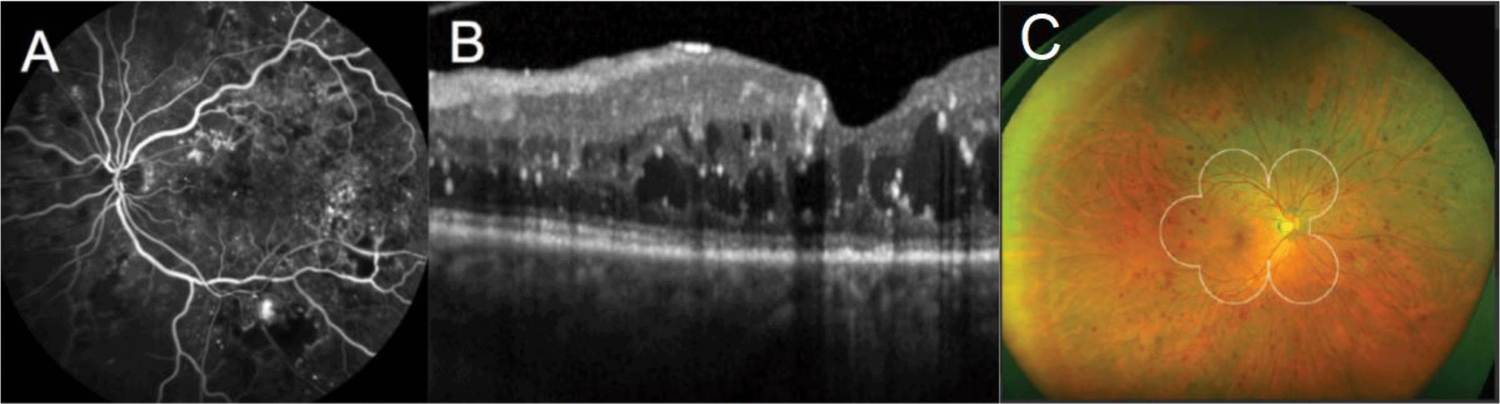

DR can be diagnosed by an optometrist or ophthalmologist with a simple examination, and in many cases, diagnosis can occur before any overt symptoms are noticed by the patient; this underscores the need for everyone, especially those with diabetes, to have regular eye exams. Tests include fluorescein angiography, which requires the intravenous injection of a contrast dye to highlight a patient’s blood vessels as broken or leaking vessels may indicate disease, or optical coherence tomography (OCT), which uses light waves to take a cross-section picture to assess the thickness of a patient’s retina. An increased thickness may indicate a buildup of fluid caused by leaky blood vessels. As a readout of treatment effectiveness, retinal thickness measured by OCT is also used in follow-up examinations to determine how disease is progressing1.

Representative images of the retina taken using (A) fluorescein angiography10, optical coherence tomography10 (B), and ultra-wide field color fundus photography11 (C; white circles show extent of standard field).